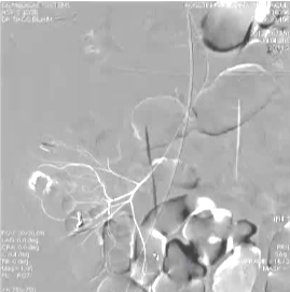

(1)操作流程·诊断性血管造影:用5F导管插管至肠系膜上/下动脉,寻找造影剂外溢(活动性出血)直接或间接征象 · · 超选择插管:通过同轴技术引入3F微导管,尽可能将导管送至直动脉(vasa recta) 或出血点最远端 · · 栓塞:首选微弹簧圈(2-3mm × 20-30mm),放置2-3个即可;也可用聚乙烯醇颗粒(>250μm);禁用液体栓塞剂(如酒精),因其肠坏死率高 · · 终点:造影证实外溢停止,同时保留近端和远端血流(不牺牲侧支循环) · (2)栓塞程度:多少算够?多少算多?理想情况:仅栓塞出血点所在的直动脉 若无法超选至直动脉,可栓塞边缘动脉(marginal artery),但必须确保:

o 近端和远端有足够的侧支血供

o 栓塞长度控制在3-4 cm以内(作者经验),避免过大范围缺血 o 栓塞的目标不是完全阻断血流,而是降低出血点的灌注压,配合局部血管痉挛和患者自身凝血能力形成血栓 5. 微导管远端栓塞临床数据:疗效与安全性一篇发表在2004年的文章汇总了12项研究【Brian Funaki 2004】、超过150例病例,核心数据如下: